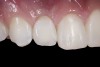

(20.) Facial view of final single-wing, modified zirconia resin-bonded bridges.

Figure 20

(21.) Smile view.

Figure 21

When the patient returned, the fit was evaluated in the mouth. Once verified, the internal surface of the framework was etched with a 9.5% hydrofluoric acid for 90 seconds and then salinized. After etching the enamel surface with phosphoric acid for 30 seconds and applying the primer (Single Bond Plus, 3M ESPE) to both the internal surface of the framework and the enamel, the zirconia bridge was bonded with a dual-cure resin cement (RelyX™ ARC, 3M ESPE). After the procedure, the patient ended up with a long-term, high-strength esthetic restoration advantaged by the bonding potential of fledspathic ceramic (Figure 20 through Figure 24). Six years after placement, the prosthesis had remained in place with no complications.